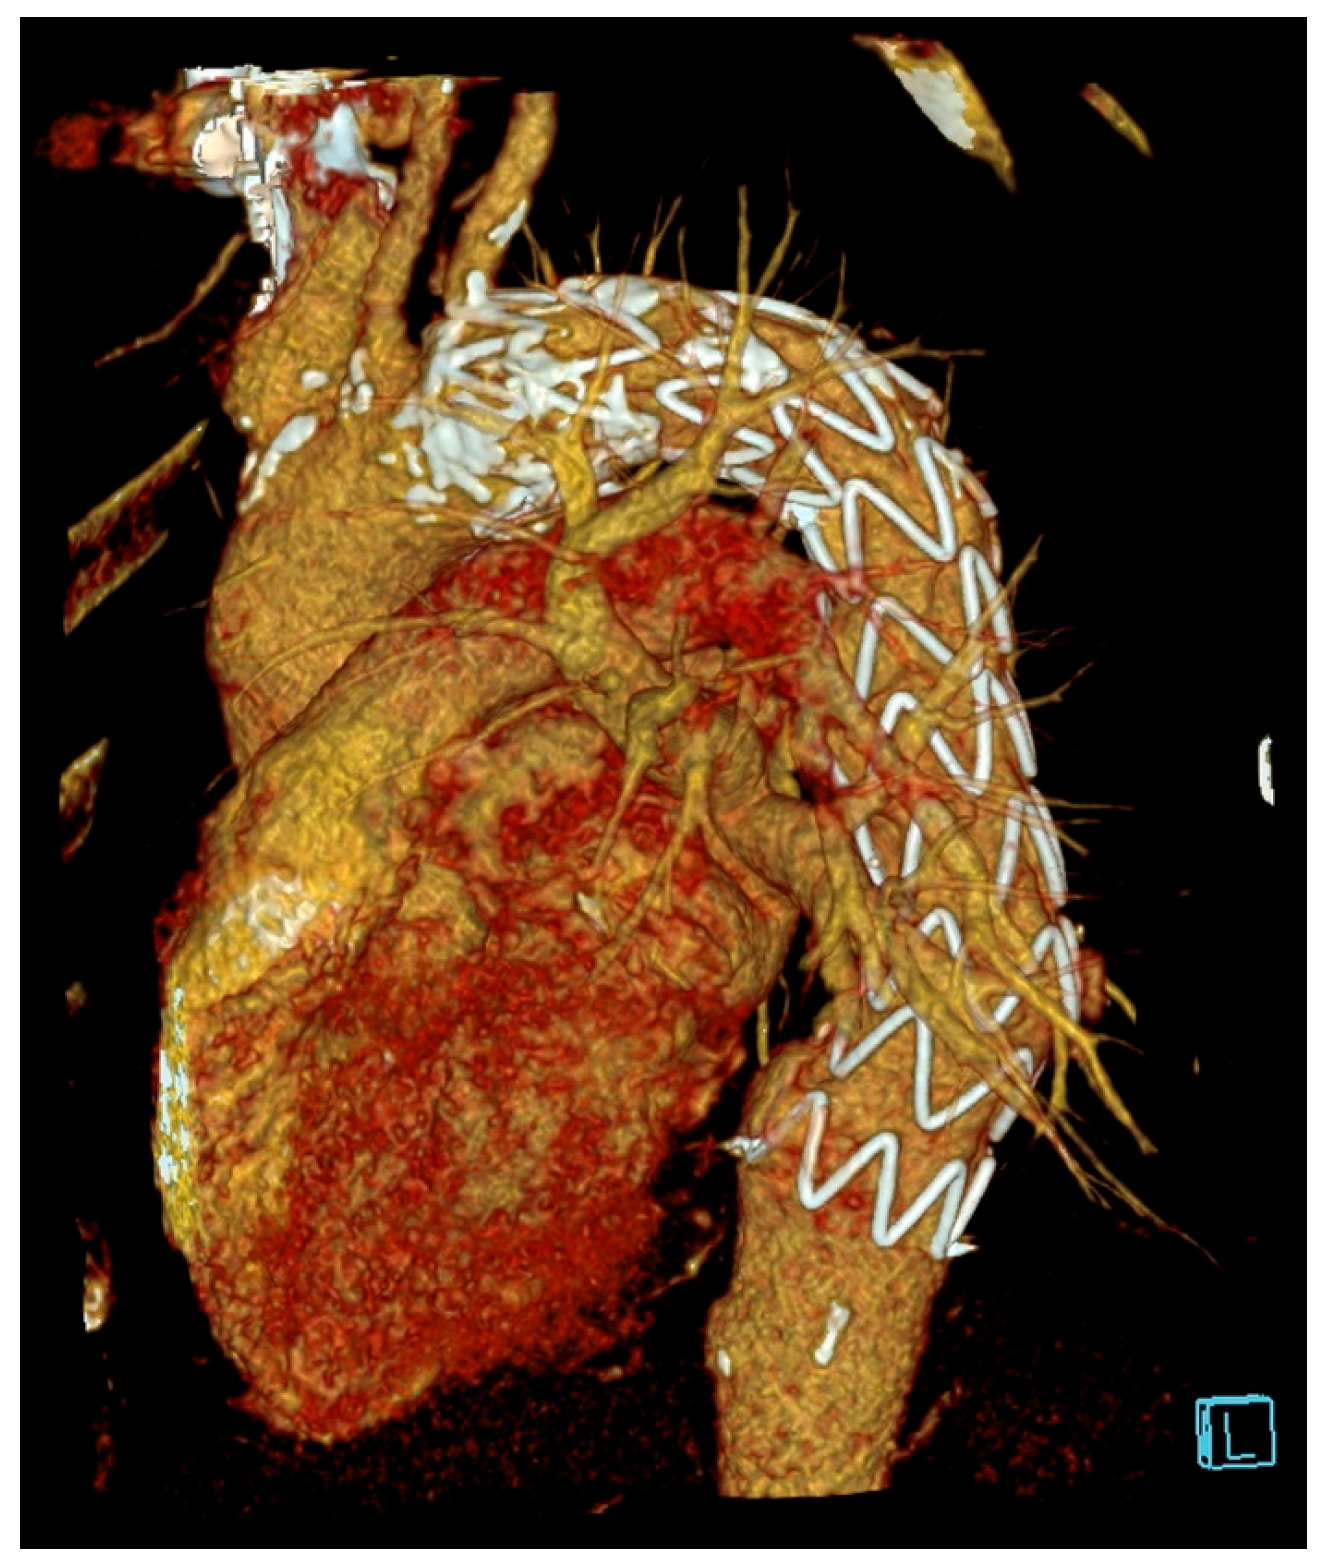

2.3. Management